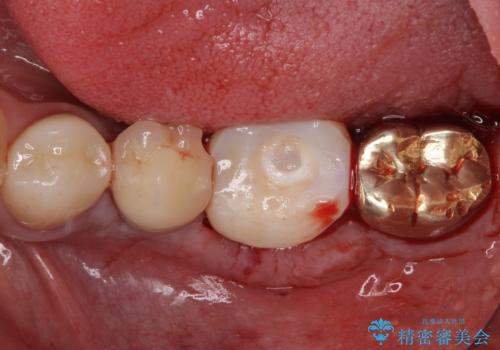

- 奥歯が割れてしまい、抜歯が必要となった患者様です。

以前にも歯が割れてインプラント治療を行いましたが、抜歯してからインプラント埋入→仮歯装着までに半年以上を要し、その間に残された歯への負担が大きくなり、セラミッククラウンが破折したことがありました。

そのため、当院に新しく導入した手法により、抜歯をした日にインプラントを埋入し、そのままを仮歯を装着することで、他の歯への負担を軽減する計画を立てました。